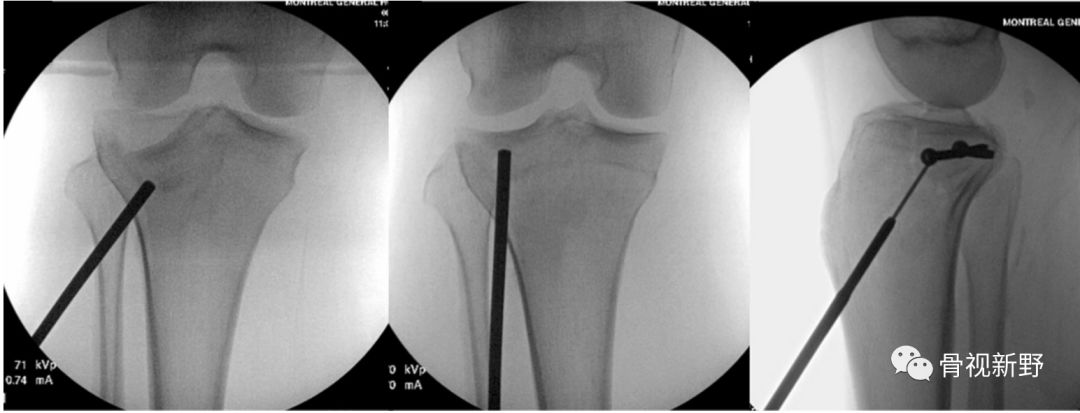

透视监测下,经皮顶棒复位塌陷的关节面,经皮在软骨下骨内打入2枚3.5-mm皮质骨螺钉作为排钉。(顶棒)骨隧道内植入8 mm *35 mm的界面螺钉(施乐辉)支撑复位的关节面。

2枚排钉和一枚前-后方向的栅栏螺钉相垂直固定。加用栅栏螺钉的目的是防止排钉对松质骨的切割。

术后6周非负重的运动,之后6周循序渐进地部分负重;术后 12月,骨折愈合;未见骨折移位、再塌陷;关节面平整,无高度丢失。

Vauclair 等人(2015)将这种栅栏螺钉+界面螺钉的组合支撑-固定技术称为“胫骨干骺端水平螺钉技术”(Metaphyseal tibia level ,MTL, screw technique),适合于骨量较好的Schatzker II、III型胫骨平台骨折的经皮微创固定。